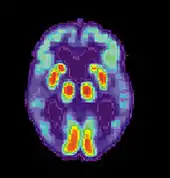

| Diagram of a normal brain compared to the brain of a person with Alzheimer's | |

AD is usually clinically diagnosed based on the person's medical history, history from relatives, and behavioral observations. The presence of characteristic neurological and neuropsychological features and the absence of alternative conditions supports the diagnosis.[108][109] Advanced medical imaging with computed tomography (CT) or magnetic resonance imaging (MRI), and with single-photon emission computed tomography (SPECT) or positron emission tomography (PET), can be used to help exclude other cerebral pathology or subtypes of dementia.[110] Moreover, it may predict conversion from prodromal stages (mild cognitive impairment) to Alzheimer's disease.[111] FDA-approved radiopharmaceutical diagnostic agents used in PET for Alzheimer's disease are florbetapir (2012), flutemetamol (2013), florbetaben (2014), and flortaucipir (2020).[112] Because many insurance companies in the United States do not cover this procedure, its use in clinical practice is largely limited to clinical trials as of 2018.[113]

Due to low accuracy, the C-PIB-PET scan is not recommended as an early diagnostic tool or for predicting the development of Alzheimer's disease when people show signs of mild cognitive impairment (MCI).[142] The use of 18F-FDG PET scans, as a single test, to identify people who may develop Alzheimer's disease is not supported by evidence.[143]